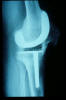

Prótesis completa de rodilla. Situación postquirúrgica.

Prótesis completa de rodilla. Situación postquirúrgica. Lateral.

Prótesis completa de rodilla.Lateral.

Prótesis completa de rodilla. Frontal.

Prótesis completa bilateral de rodillas.